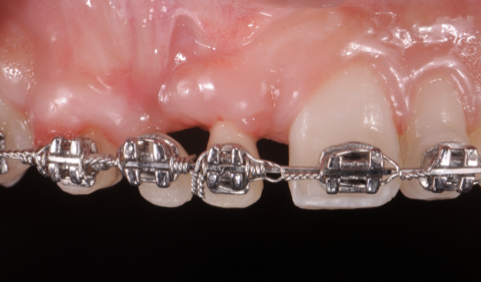

The patient had a congenitally missing upper right lateral incisor. Orthodontic treatment was performed to create the necessary space for a dental implant. Unfortunately, the implant failed, and so did several subsequent attempts to bone graft. These failures resulted in a visible smile deformity, that got worse after each failed procedure.

After the 3rd bone graft failed, the patient sought second opinions. She was a college sophomore at the time. Using a combination of interdisciplinary therapies, including S.M.A.R.T. minimally invasive bone grafting, Dr. Ernesto Lee was able to tridimensionally reconstruct this severe defect and place implants to restore the patient’s smile. The S.M.A.R.T. bone graft was also extended to treat adjacent teeth with thin/dehisced bone.